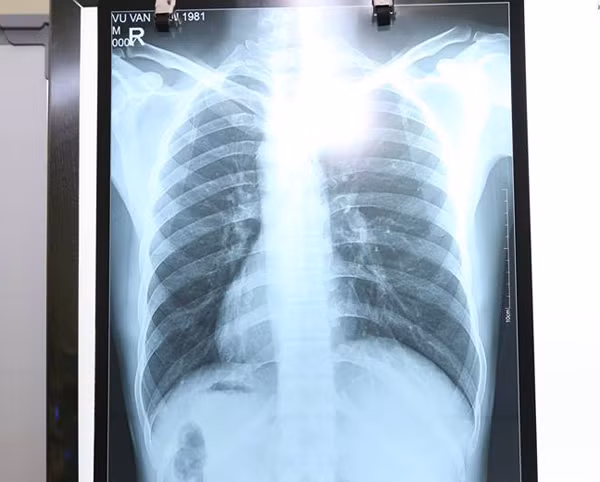

Tuy nhiên, điều khiến các bác sĩ kinh ngạc là tim cùng các phủ tạng khác trong lồng ngực và bụng của bệnh nhân đều ở vị trí ngược so với bình thường, tim và dạ dày đều ở bên phải còn gan, ruột thừa nằm ở bên trái.

| Tim, dạ dày và nhiều cơ quan nội tạng khác của bệnh nhân H. đều ở vị trí lộn ngược so với người bình thường. |

Theo BS Hà, đây là một trường hơp cực kỳ hiếm gặp. Với trường hợp thông thường, đau ruột thừa sẽ đau ở hố chậu phải vì vị trí manh tràng nằm bên phải, nhưng trường hợp này, bệnh nhân H. lại đau bên trái.